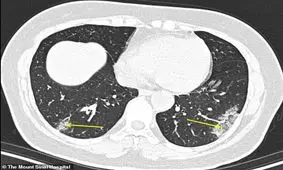

پژوهشگران اخیراً اعلام کردهاند با کمک سیتی اسکن میتوان بیماری مهلک کروناویروس را چهار روز زودتر تشخیص داد.

تامین اجتماعی اعلام کرد: پزشکان عمومی میتوانند سیتی اسکن ریه درخواست کنند